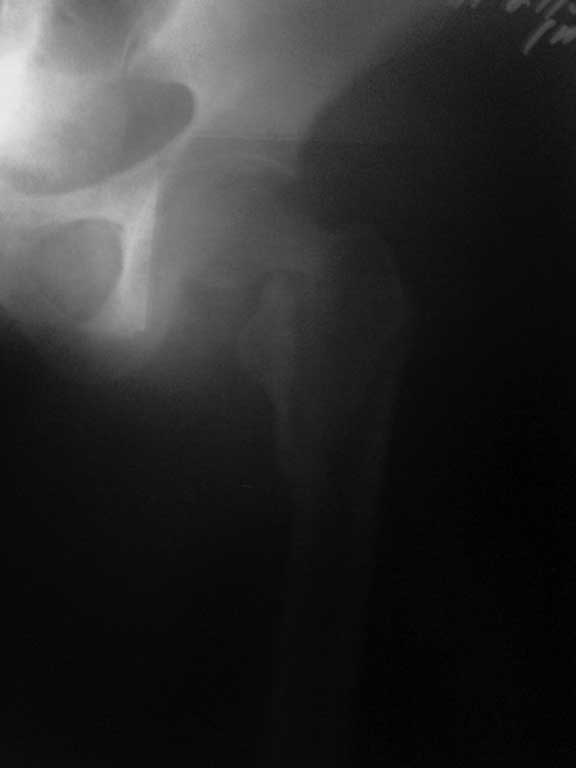

Снимок, конечно, паршивый - лучше было повременить с размещением вопроса до возможности сопроводить его нормального качества иллюстрациями.

Перелом идет на диафиз, так что если придется использовать пластину, то надо длинную, да с угловой стабильностью - клинковую, может.

Тут, видимо, лучше использовать реконструкционный гвоздь - не знаю, какова на месте степень недоступности такого типа имплантатов. Где вы находитесь? Может, попытаться прислать подходящую железку?

Хотелось услышать дискуссию, по-этому выложил некачественный снимок с вопросом. Стараюсь выложить немного лучше. Гамму она приобрести не сможет. Смущает то что шейка больно хлипкая и винтом развалим ее до конца. На снимке кажется что и фрагмент шейки также сломан вдоль.

Нет КТ - качественный Рн нужен. Консервативное лечение здесь не рассматривается, как однозначно калечащее. Видно - нужно быть готовым к открытой репозиции. Винты не обеспечивают достаточной стабильности при такой линии излома. И, даже если бы была возможность ИМ фиксации, я бы предпочёл Динамический Бедренный Винт (так правильно?) в этом случае. Черкните мне, или позвоните, если нужна поддержка, приеду, помогу по соседски-то. Вы же в Коньково? Андрей

Этот случай не является типичным, я бы рассматривал его с точки зрения механики как комбинацию (редкую, надо сказать, комбинацию) латерального и медиального переломов. Если я правильно могу прочитать представленные рентгенограммы, конечно. И нестабильным как раз в данном случае является медиальный компонент повреждения. Поэтому выбор технологии диктуется медиальым, сложным компонентом. Для латерального по большому счёту всё равно - гвоздь или Динамический Бедренный Винт. Для базисцервикальной шейки же гвоздь не даёт особых преимуществ. Репозиция, скорее всего, будет октрытой. Поэтому, DHS в комбинации (если войдёт)с дополнительным антиротационным винтом. Но, -прежде всего, рентгенография нужна приемлемого качества. Так я бы рассуждал, если бы это был наш пациент. С уважением, Андрей